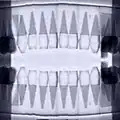

joined images to panoramic

joined images to panoramic -